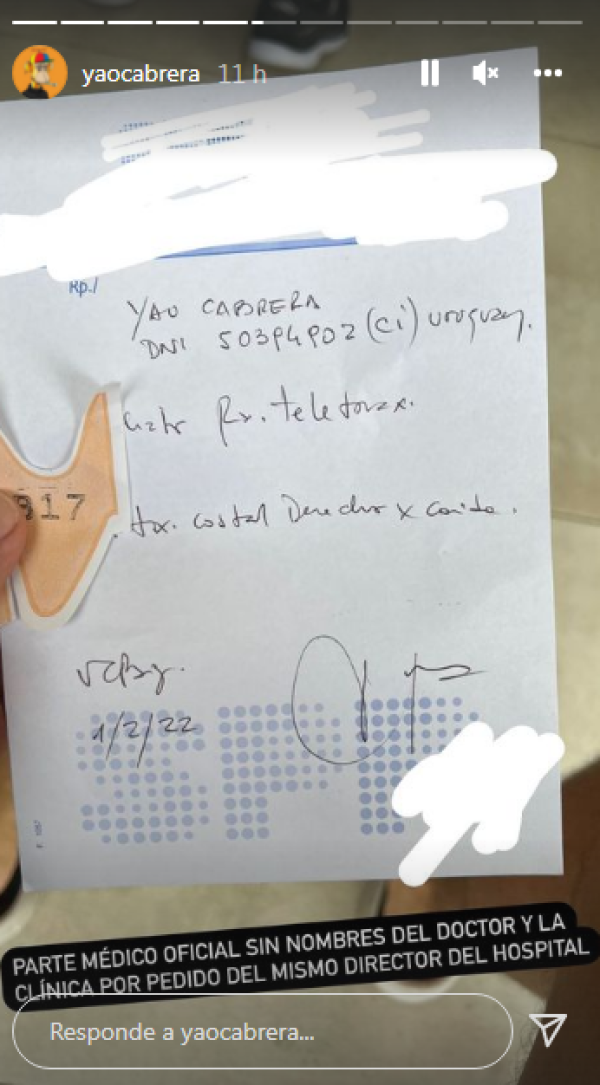

El propio Yao compartió en su cuenta de Instagram una serie de imágenes que dejan en claro que su caída fue real: